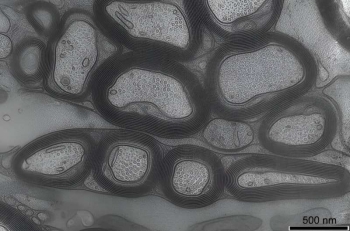

Credit: Wiebke Moebius, MPI Goettingen.

Research suggests myelin fatty acid metabolism could serve as an energy reserve for the central nervous system

These findings suggest that oligodendroglial lipid metabolism can serve as an energy reserve, helping to overcome glucose deprivation and associated neurodegeneration.